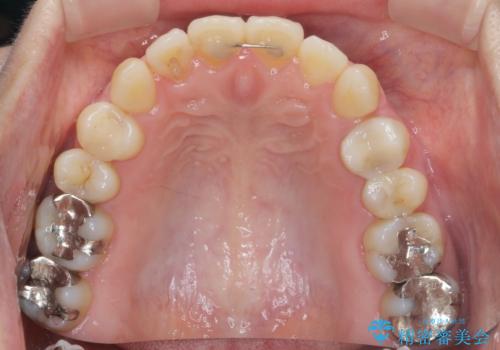

銀歯をゼロに! 短期間で行うメタルフリー治療

- 口の中に見える銀歯を、金属アレルギーの対策と審美性の向上のため全て除去したい!と希望され来院されました。

銀歯を丁寧に除去したのち、精度の良いセラミックインレー、セラミッククラウンで修復・補綴処置を行っていきます。

- 62.7万円(ジルコニアクラウン×3・仮歯×3・セラミックインレー×3)費用は治療当時の料金となります